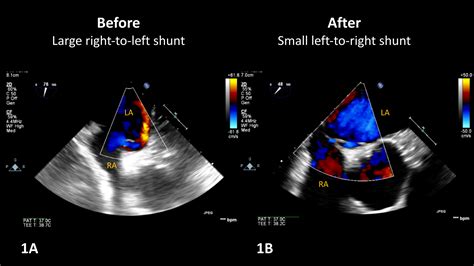

Understanding the complexities of the human circulatory system is essential for recognizing how oxygenated and deoxygenated blood interact. Under normal physiological conditions, the heart pumps blood in a highly organized circuit: deoxygenated blood travels to the lungs for gas exchange, returns as oxygenated blood, and is then distributed to the rest of the body. A Right To Left Shunt represents a significant disruption to this pathway. When this occurs, blood bypasses the pulmonary circulation—the lungs—entirely, moving directly from the right side of the heart to the left side. Because this blood has not been oxygenated, it introduces deoxygenated blood into the systemic circulation, which can have profound clinical implications.

In a healthy individual, the pressure in the left side of the heart is significantly higher than in the right side. This pressure gradient ensures that blood flows forward and does not move backward or across the septum. A Right To Left Shunt typically develops when anatomical defects allow blood to follow the path of least resistance or when pulmonary resistance becomes so elevated that it forces blood across these abnormal connections.

• Eisenmenger Syndrome: A state where a pre-existing left-to-right shunt (like a large VSD) leads to pulmonary hypertension, eventually reversing the flow to a Right To Left Shunt.

The management of a Right To Left Shunt depends heavily on the severity of the symptoms and the underlying structural cause. In many pediatric cases, surgical intervention is the gold standard. Procedures aim to either close the septal defect or reroute the great vessels to restore normal circulation. For patients with milder symptoms or those who are not candidates for surgery, medical management focuses on optimizing oxygenation and monitoring for potential complications such as stroke or endocarditis.